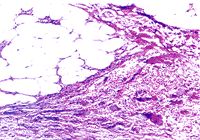

尿石的病理變化主要是由結石對組織造成的創傷和對尿液引流的梗阻以及並發感染所引起結石處可有上皮脫落、組織潰瘍和纖維組織增生。長期結石創傷可使腎盂壁變厚,間質組織纖維增生和白細胞浸潤。一般尿石對尿液引流造成梗阻和使結石的近端尿路積水,尤其是腎盂積水但梗阻常不是完全性的腎盂積水時見腎小盞變鈍和有不同程度的小盞擴大。病情進一步發展時,可形成腎皮質萎縮和損壞擴大的腎盞可使腎皮質變得很薄。如結石性腎盂積水並發感染,則可成為膿性結石性腎盂積水,加速腎實質的損壞感染尚可引起腎周圍炎和腎周圍膿腫。